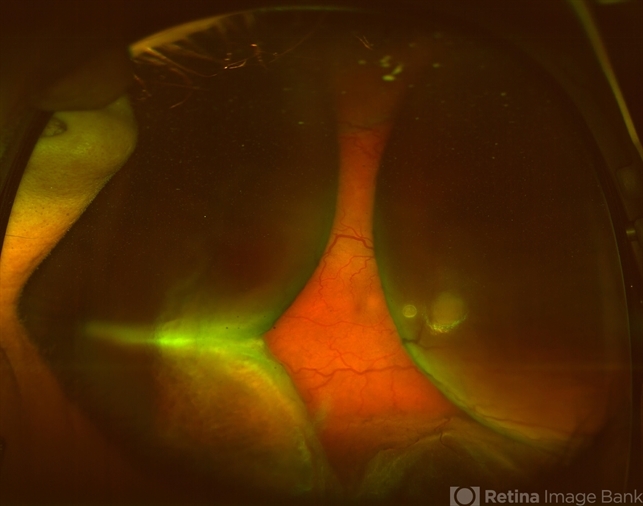

By Sharon Fekrat, MD FACS FASRS

Duke University School of Medicine - Uploaded on Oct 15, 2012.

- choroidal effusion

- Duke University Eye Center, Durham, NC

- Fundus camera

- 54-year-old female with nanophthalmos and choroidal effusions.